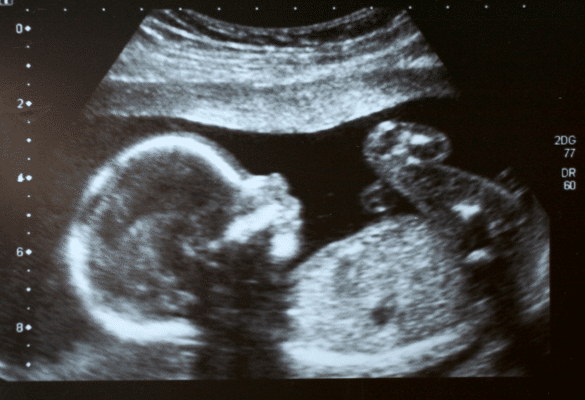

Le sexe de bébé est déterminé dès la conception. On ne peut le voir de manière fiable qu’à partir de l’échographie morphologique, généralement vers 22 semaines d’aménorrhée ( environ 5 mois de grossesse, comptés depuis le premier jour des dernières règles).

L’échographie morphologique est considérée comme fiable à environ 95 % si bébé est bien positionné.

La plupart des parents découvrent son sexe lors de la deuxième échographie, dite échographie morphologique. C’est à ce moment que le médecin peut visualiser les organes génitaux… si bébé accepte de bien se positionner et que le placenta ne masque pas la vue.